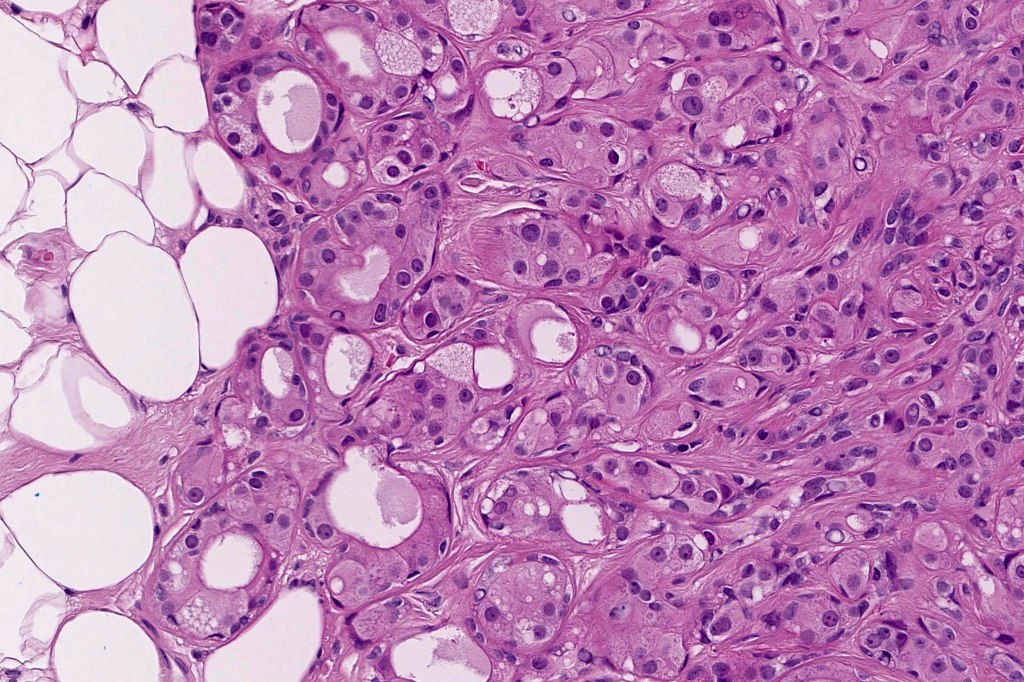

•Large cells with vesicular nuclei and often prominent nucleoli

•Decapitation secretion

•Variable pleomorphism, mitotic activity & atypical mitoses

•Variable necrosis

•Variable lymphovascular involvement & perineural infiltration

•Exceptionally squamous, clear cell, granular cell and sebaceous differentiation

•Intracytoplasmic DPAS +ve granules